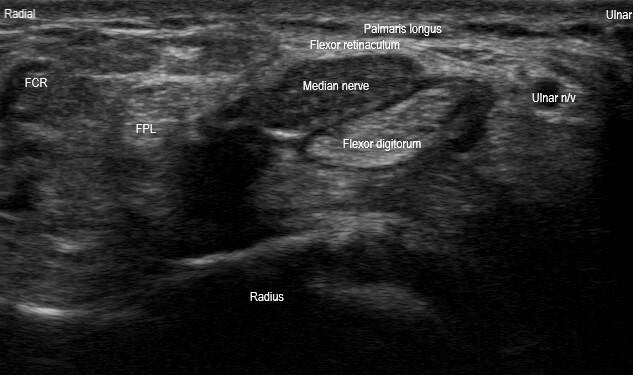

These are long and short axis images of the carpal tunnel. The long axis image (top) demonstrates fusiform swelling, hypoechoic thickening, loss of normal fascicular pattern, and notching of the median nerve at the carpal tunnel inlet. The short axis image (bottom) demonstrates hypoechoic thickening and loss of normal fascicular pattern of the median nerve. There is also bowing of the wrist flexor retinaculum. The median nerve cross-sectional area measures approximately 33 millimeters², which is significantly larger than the normal average of 8-9 millimeters². These findings suggest severe carpal tunnel syndrome.